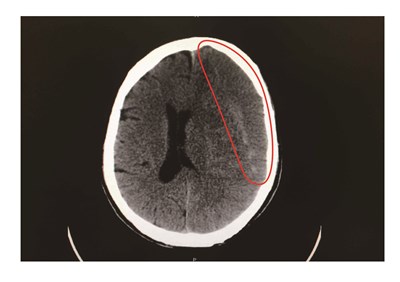

65歲廖姓男子日前工作時遭木板砸頭,當下不以為意,隔天起床卻出現右側手腳明顯無力,經就醫確診為慢性硬腦膜下出血。圖/中央社

【本報台中訊】65歲廖姓男子日前工作時遭木板砸頭,當下不以為意,隔天起床卻出現右側手腳明顯無力,經就醫確診為慢性硬腦膜下出血,經緊急手術引流後才逐漸康復。

林牧熹說,腦部受撞擊後,可能在硬腦膜下腔形成血腫,如果血腫小、沒明顯症狀,正常身體會慢慢吸收,但有些人可能因體質或年紀大伴有腦萎縮等原因,身體無法被完全吸收血腫,隨時間增長,血腫愈來愈嚴重即形成慢性硬腦膜下腔出血,逐漸壓迫到大腦。